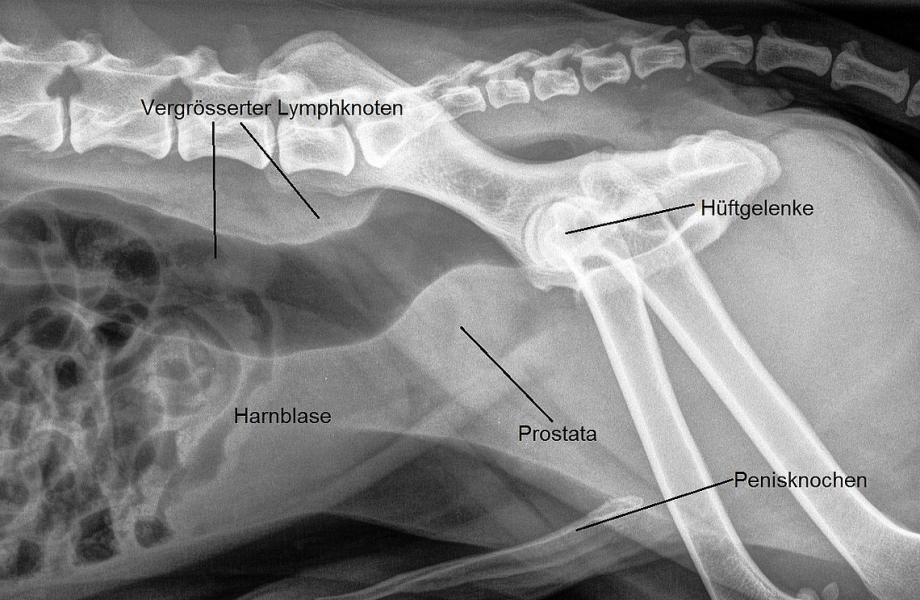

Zur Abklärung eines möglichen Blasen- oder Prostataproblems wird zuerst ein Röntgenbild angefertigt. Hier sieht man, dass die Prostata vergrössert ist (was bei einem kastrierten Rüden ungewöhnlich ist) und der Enddarm vor dem Beckeneingang etwas gegen unten gedrückt erscheint - möglicherweise wird dies durch vergrösserte Lymphknoten in dieser Gegend bewirkt.

Anschliessend wird die Bauchhöhle mittels Ultraschall untersucht: Tatsächlich erscheinen die Beckeneingangs-Lymphknoten vergrössert. Die Prostata präsentiert sich vergrössert und mit stark variabler Echotextur; sie enthält einen flüssigkeitsgefüllten Hohlraum (zB Cyste oder Abszess) und stellenweise sind auch Verkalkungen zu sehen. Die Harnblase erscheint unauffällig.